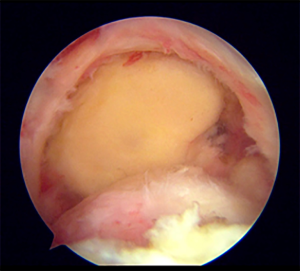

Glenoid site preparation

The glenoid side was prepared with the combination of radiofrequency ablation device, arthroscopic shaver, and burr after graft preparation. The remaining labrum should be cleared off from the glenoid surface. The long head of the biceps was usually very frayed and tenotomized. The superior margin of the glenoid was debrided to allow at least 3 suture anchors for fixation (JuggerKnot®, 2.5 mm; Zimmer Biomet, IN, USA or Suturefix Ultra anchor®, 1.9 mm; Smith & Nephew, MA, USA) at the 10, 12, and 2 o’clock positions (Figure 4). Neviaser or accessory portal may be used to assist with the glenoid anchor placement. Care should be taken not to injure the cartilage enface of the glenoid. All soft suture anchors with smaller dimensions were preferred with the argument to avoid suprascapular nerve injury.